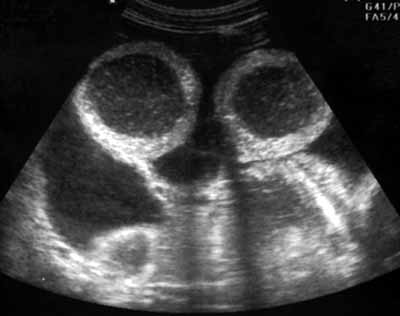

Ультразвуковое исследование в диагностике тонкокишечной непроходимости.

Рис. 2. Тот же больной. Поперечное сканирование.

Новости лучевой диагностики 2002 1-2: 32-34